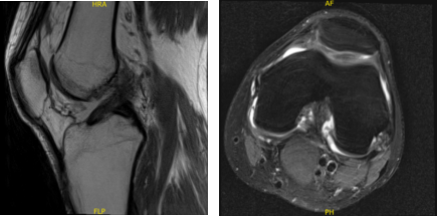

For his MRI, the result showed abnormal morphology of the ACL likely related to partial disruption or possibly complete disruption (images limited by motion). Medial meniscus bucket-handle tear.

MRI-3T Left knee non-contrast